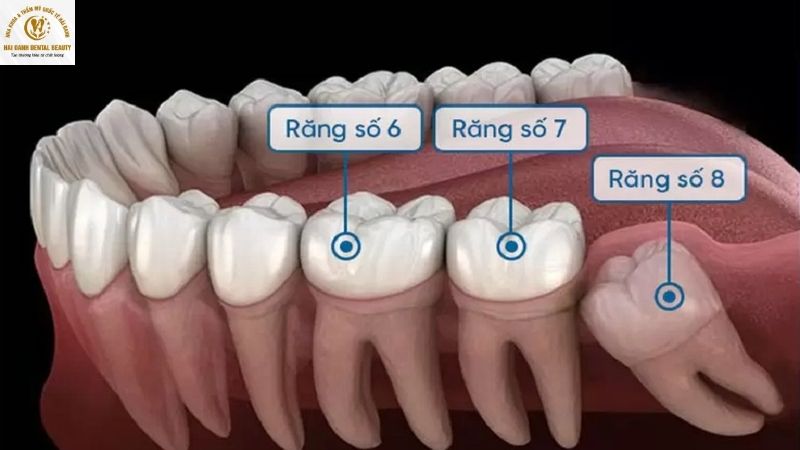

Răng khôn (hay còn gọi là răng số 8, răng hàm lớn thứ ba) là chiếc răng mọc cuối cùng trên cung hàm, thường xuất hiện ở những người thuộc độ tuổi 17 đến 25. Sự xuất hiện muộn và thường xuyên gây rắc rối, khiến răng khôn trở thành một trong những vấn đề nha khoa được quan tâm nhất.

Thông thường, một người có đủ bộ răng vĩnh viễn là 32 chiếc, bao gồm 28 răng thông thường và thêm 4 chiếc răng khôn. Bốn chiếc răng khôn này, hay còn gọi là răng số 8, nằm ở vị trí cuối cùng của cung hàm, mỗi chiếc ở một góc phần tư (trên-trái, trên-phải, dưới-trái, dưới-phải). Chúng thường mọc sau 28 chiếc răng còn lại.